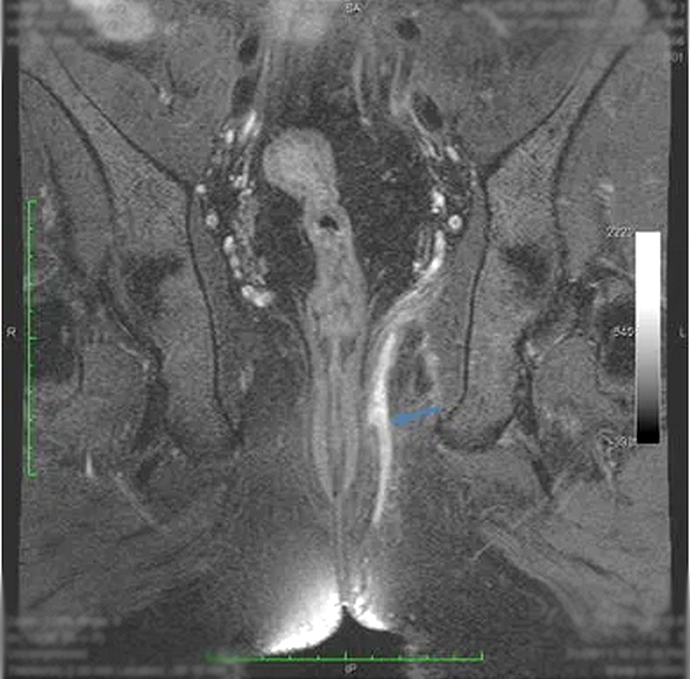

Chụp cộng hưởng từ rò hậu môn bao gồm hai giai đoạn trước tiêm thuốc và sau tiêm thuốc đối quang từ (tương phản từ). Mục đích chính của việc sử dụng thuốc đối quang từ là giúp hiện hình rõ đường rò và đánh giá mô xung quanh đường rò. Mặc dù phản ứng Dị ứng ít khi xảy ra với thuốc đối quang từ, bác sĩ sẽ hỏi bạn về tiền sử sử dụng thuốc cũng như tư vấn cho bạn lợi ích và nguy cơ của thuốc trong từng trường hợp cụ thể.

Một ca chụp cộng hưởng từ rò hậu môn khoảng 30-45 phút. Bạn sẽ nằm trên giường chụp và kỹ thuật viên sẽ đặt một thiết bị đặc biệt gọi là “Coil” quanh vùng bụng – chậu của bạn. Bàn chụp sẽ được đưa vào trong “lồng” và kỹ thuật viên sẽ bắt đầu lấy hình ảnh vùng chậu, bao gồm hậu môn và vùng xung quanh hậu môn. Bạn sẽ được kỹ thuật viên tiêm thuốc giữa quá trình chụp. Sau khi tiêm thuốc, đường rò hậu môn sẽ nổi rõ hơn trên hình ảnh, giúp bác sĩ nhận diện và đánh giá tổn thương tốt hơn.

Bên cạnh các phương tiện như X-quang, CT Scan, Nội soi đại trực tràng, siêu âm đường hậu môn... cộng hưởng từ là một phương tiện tiên tiến để đánh giá và phân loại đường rò hậu môn. Cộng hưởng từ có nhiều ưu điểm trong mô Tả chính xác vùng giải phẫu quanh hậu môn, đánh giá được mối liên quan giữa đường rò với hoành chậu (cơ nâng) và hố trực tràng. Đây là một phần quan trọng giúp các bác sĩ ngoại khoa trước phẫu thuật.

Bác sĩ Chẩn đoán hình ảnh sẽ phân tích và đưa ra kết quả dựa trên hình chụp qua từng lát cắt mỏng vùng chậu. Qua đó, đường rò của bạn sẽ được phân loại dựa theo bảng phân loại hiện có. Đồng thời, nhu mô xung quanh đường rò sẽ được đánh giá và ghi nhận những bất thường đáng chú ý, trong đó có những biến chứng của đường rò (ví dụ nhiễm trùng, áp xe, đường rò tái phát...).